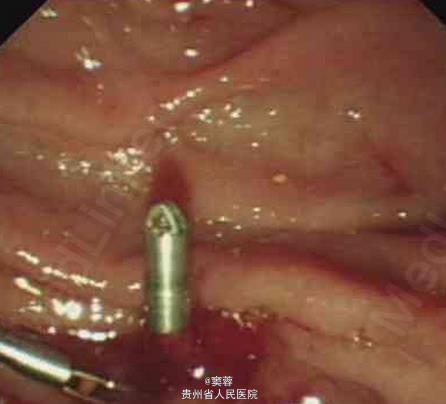

患者男性,60岁,有慢性胆囊炎及胆囊结石病史20年。患者于2006年6月中旬无诱因出现尿黄、皮肤黄,无腹痛、发热等,在当地医院接受经内镜逆行胰胆管造影(ERCP)及胆管塑料支架置入引流。ERCP造影提示患者有肝门部占位。